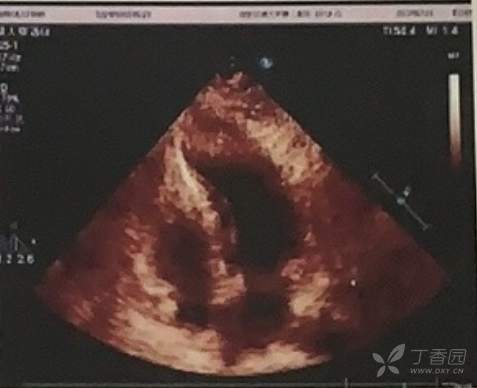

超声检查示:

二维数据:LA:38 A0根部:24 AA0:36 RVOT:22 MPA:20 LV:31x75,RV:28x60,LA:36x65,RA:28x40;

M型数据:IVSmm:幅度:9 舒张期末厚度:18.5;

LVPWmm:幅度:9 舒张期收缩期末:13

LV前后径mm:舒张期末:40 收缩期末:27

左心功能测定:EF:0.62 FS%:33

左房增大,升主动脉增宽,各房室腔及肺动脉内径测值正常范围。各组瓣叶回声正常,运动自如。

左室壁增厚,前壁厚22,侧壁19mm,后壁14mm,下壁21mm,左室心腔狭小,呈“葫芦状”,舒张末容积35ml,心尖部未见明确室壁瘤形成,收缩期左室腔中段流速增快,Vmax:413cm/s,PG:68mmHg,运动幅度正常;左室流出道内径12mm,流速增快,Vmax:436cm/s,PGmax:76mmHg,PGmean:25mmHg;左心功能测值正常;心包腔未见异常。

PW:二尖瓣口瓣上血流频谱A峰>E峰

CW+CDFI:二尖瓣返流彩束面积2.0cm2

图:超声心动图图像

结论:肥厚性心肌病(梗阻型),左室流出道梗阻 (中-重度);左房增大,升主动脉增宽;左心收缩功能测值正常范围,舒张充盈受限